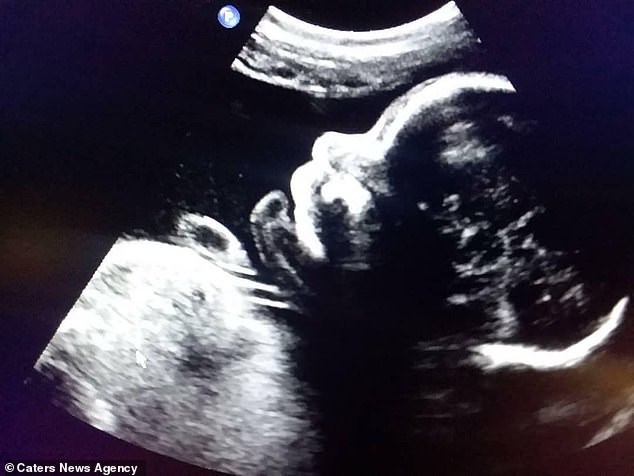

Ένα υγιέστατο αγοράκι έφερε στη ζωή ο 28χρονος Γουίλεϊ Σίμπσον από το Τέξας των ΗΠΑ. Ο άνδρας ήταν γυναίκα και άρχισε την ορμονοθεραπεία στα 21 του προκειμένου να γίνει άνδρας. Ο Γουίλεϊ είναι αρραβωνιασμένος με τον επίσης 28χρονο Στέφεν Γκάεθ και αποφάσισαν να φέρουν στον κόσμο το παιδί τους παρά τους αρχικούς ενδοιασμούς. Αν και οι γιατροί του είχαν πει ότι δεν θα μπορούσε να μείνει έγκυος καθώς δεν είχε πλέον περίοδο. Τον Φεβρουάριο του 2018 το ζευγάρι πληροφορήθηκε ότι θα αποκτούσε παιδί και πριν από έξι υποδέχθηκε τον μικρούλη Ρόουαν.

Ανακάλυψε ότι είναι έγκυος στην 11η εβδομάδα καθώς είχε πρωινές ναυτίες και είχε συναισθηματικές διακυμάνσεις.